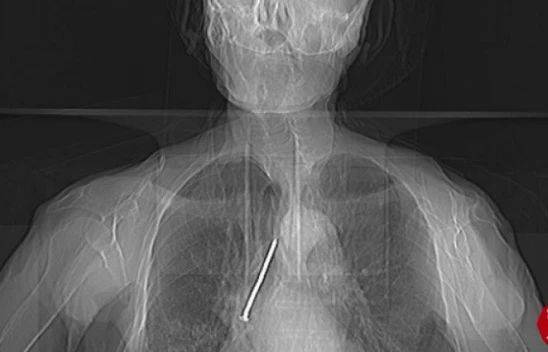

Soluk Borusuna Kaçan 10 Santimlik Çivi Çıkarıldı

Elazığ'da, hastaneye başvuran 91 yaşındaki Keko Ateş'in nefes borusuna kaçan 10 santimetrelik inşaat çivisi, yapılan operasyonla başarılı bir şekilde çıkarıldı.